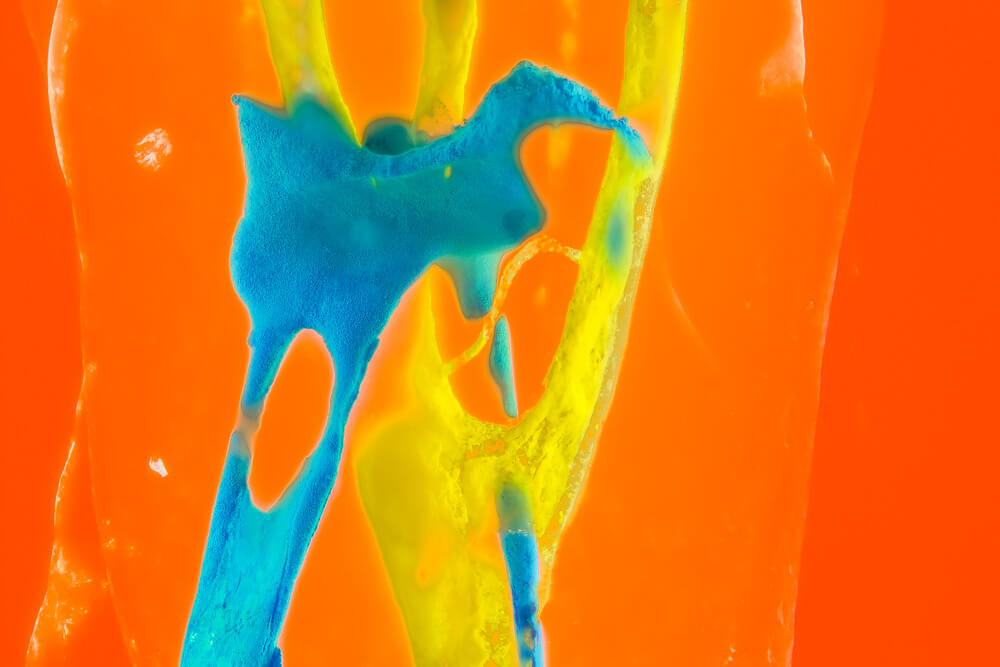

Bildauswahl Pop Art

- Foto hinter 3mm Acrylglas, rahmenlos

- hochwertige, unsichtbare Aufhängung, "schwebend“

- Hoher UV-Schutz für lang anhaltend strahlende Farben

- Bruchsicher und leichter als Glas

- Beeindruckende Farben und brilliante Tiefenwirkung

- Druck erfolgt ohne Wasserzeichen

- Bildgröße Variante 1: 90 x 120 cm

- Preis auf Anfrage, zuzüglich 20,90 Euro Versand & Porto innerhalb Deutschlands, weiterer Versand auf Anfrage

- Bildgröße Variante 2: 90 x 90 cm, quadratisch

- Preis auf Anfrage, zuzüglich 20,90 Euro Versand & Porto innerhalb Deutschlands, weiterer Versand auf Anfrage

- Bildgröße Variante 3: 60 x 120 cm, Hochformat

-

Preis auf Anfrage, zuzüglich 20,90 Euro Versand & Porto innerhalb Deutschlands, weiterer Versand auf Anfrage

Wenn Sie Interesse an den Fotos transparenter Zahnpräparate haben, bieten wir hier die Möglichkeit einige Versionen als Acrylbilder (alle Detailinformationen zu Größe und Preis siehe obige Auswahl) zu bestellen.

Die Bilder sind nicht nur zur Praxisverschönerung geeignet sondern auch eine wertvolle Unterstützung bei der Patientenberatung vor endodontischen Behandlungen.